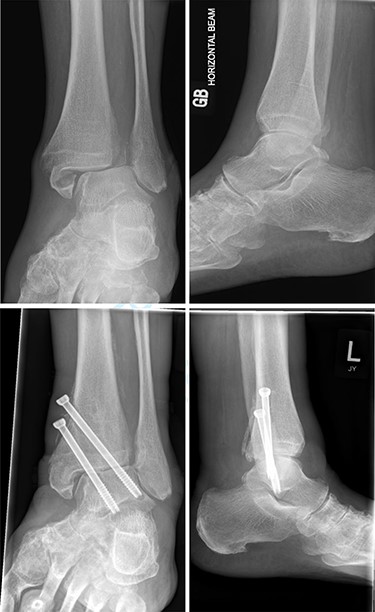

Overall, four out of six patients (66.7%) had satisfactory post-op radiographs with no evidence of talar shift, non/mal-union, widening of the syndesmosis or screw loosening (Figs 1 and 2).

Top—Bimalleolar ankle fracture with talar shift. Bottom—Radiographs at 3 months follow-up showing maintained tibiotalar alignment.

Top—Fracture dislocated bimalleolar ankle fracture. Bottom—6 weeks post-operatively showing maintained tibiotalar alignment.